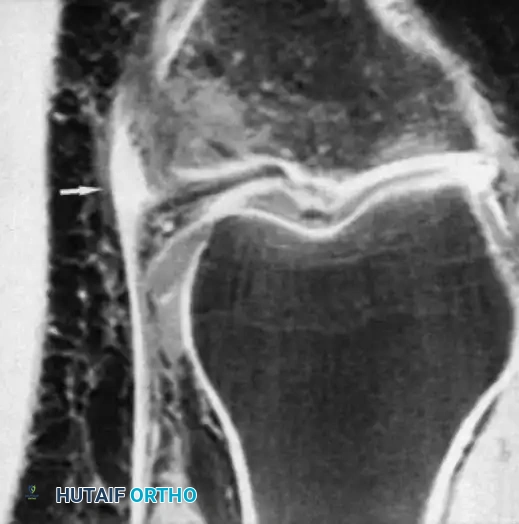

DIAGNOSTIC EVALUATION

History and Mechanism

A meticulous history often yields the diagnosis before the physical examination begins. The surgeon must ascertain the position of the knee at the time of injury, the weight-bearing status, the direction of the applied force, and the sensation of a "pop" or tearing.

The timing of swelling is a critical diagnostic clue. Rapid intra-articular swelling (within 1 to 2 hours) strongly suggests a hemarthrosis, indicative of an ACL tear, osteochondral fracture, or peripheral meniscal tear. Conversely, swelling that develops gradually overnight usually indicates an acute traumatic synovitis.

Physical Examination

The examination must be precise, systematic, and performed as soon as possible before severe swelling and involuntary muscle guarding obscure the findings. Both lower extremities must be fully exposed for comparison.

Image

Observe for ecchymosis, abrasions, and the resting attitude of the limb. Muscle atrophy, particularly of the vastus medialis obliquus (VMO), occurs rapidly following knee trauma and should be noted.

Palpation of the collateral ligaments from their femoral origins to their tibial/fibular insertions is necessary to localize the exact site of pathology. A palpable defect is occasionally present immediately after injury, particularly at the tibial insertion of the MCL or the fibular insertion of the LCL.

Stress testing is the cornerstone of the physical examination. Valgus and varus stress tests should be performed at both 0 degrees (testing the capsule and cruciates) and 30 degrees of flexion (isolating the collateral ligaments). The Lachman test, anterior drawer, and pivot-shift tests evaluate the ACL, while the posterior drawer and dial tests evaluate the PCL and posterolateral corner.